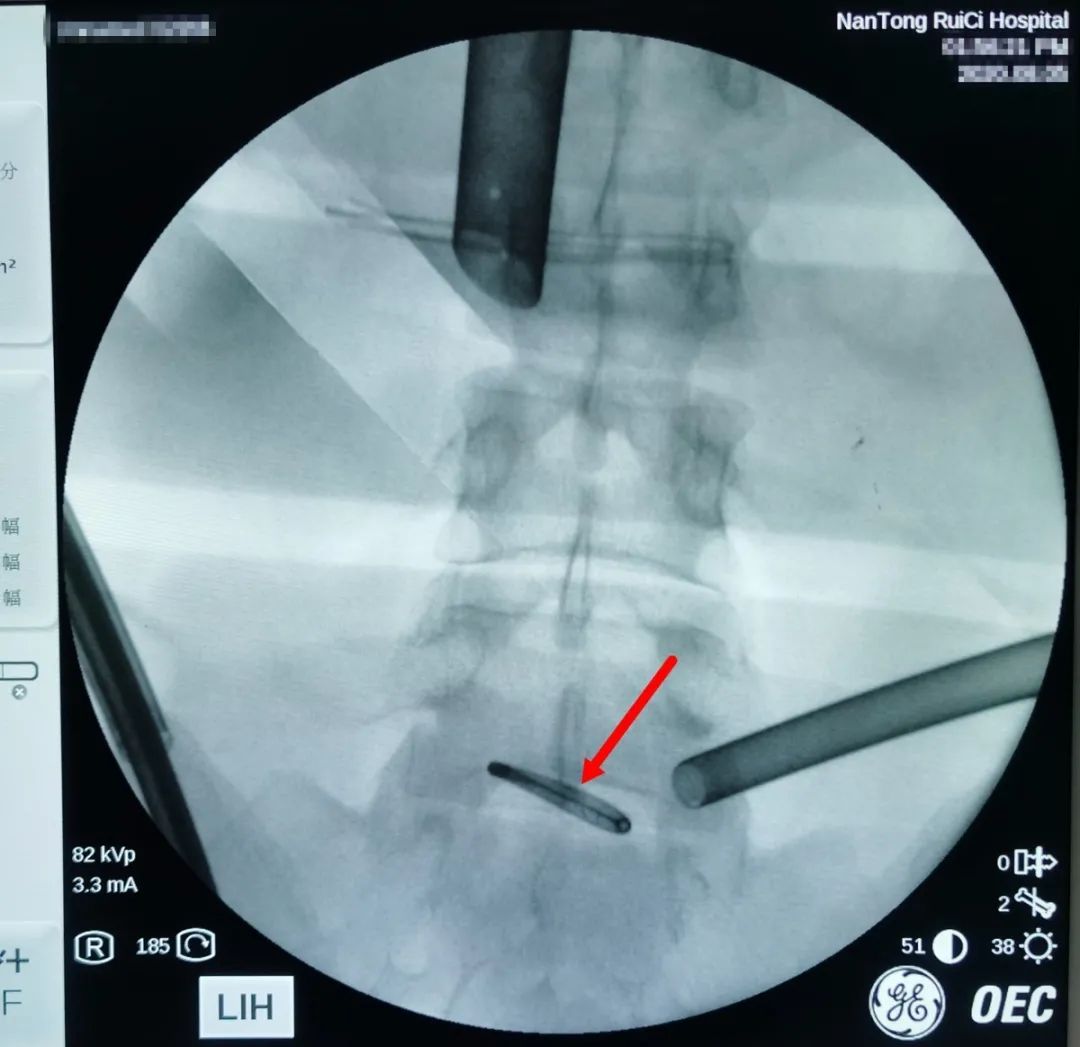

△通過術(shù)中X光,對(duì)節(jié)育環(huán)進(jìn)行標(biāo)記定位。

通過反復(fù)的X光定位,醫(yī)生終于發(fā)現(xiàn)了節(jié)育環(huán)的蹤跡,這枚“O”型節(jié)育環(huán)已經(jīng)跑到了乙狀結(jié)腸中段右側(cè)系膜內(nèi),并且穿透了乙狀結(jié)腸右側(cè)壁肌層,貫穿腸腔。醫(yī)生分離切開腸系膜后,看見有近一半的節(jié)育環(huán)嵌頓在腸腔內(nèi)。

△上圖為吳主任曾經(jīng)接診一位患者,由于節(jié)育環(huán)放置時(shí)間過長(zhǎng),嵌頓在子宮肌層,在外院取環(huán)失敗,節(jié)育環(huán)斷裂穿出子宮,差點(diǎn)進(jìn)入膀胱。